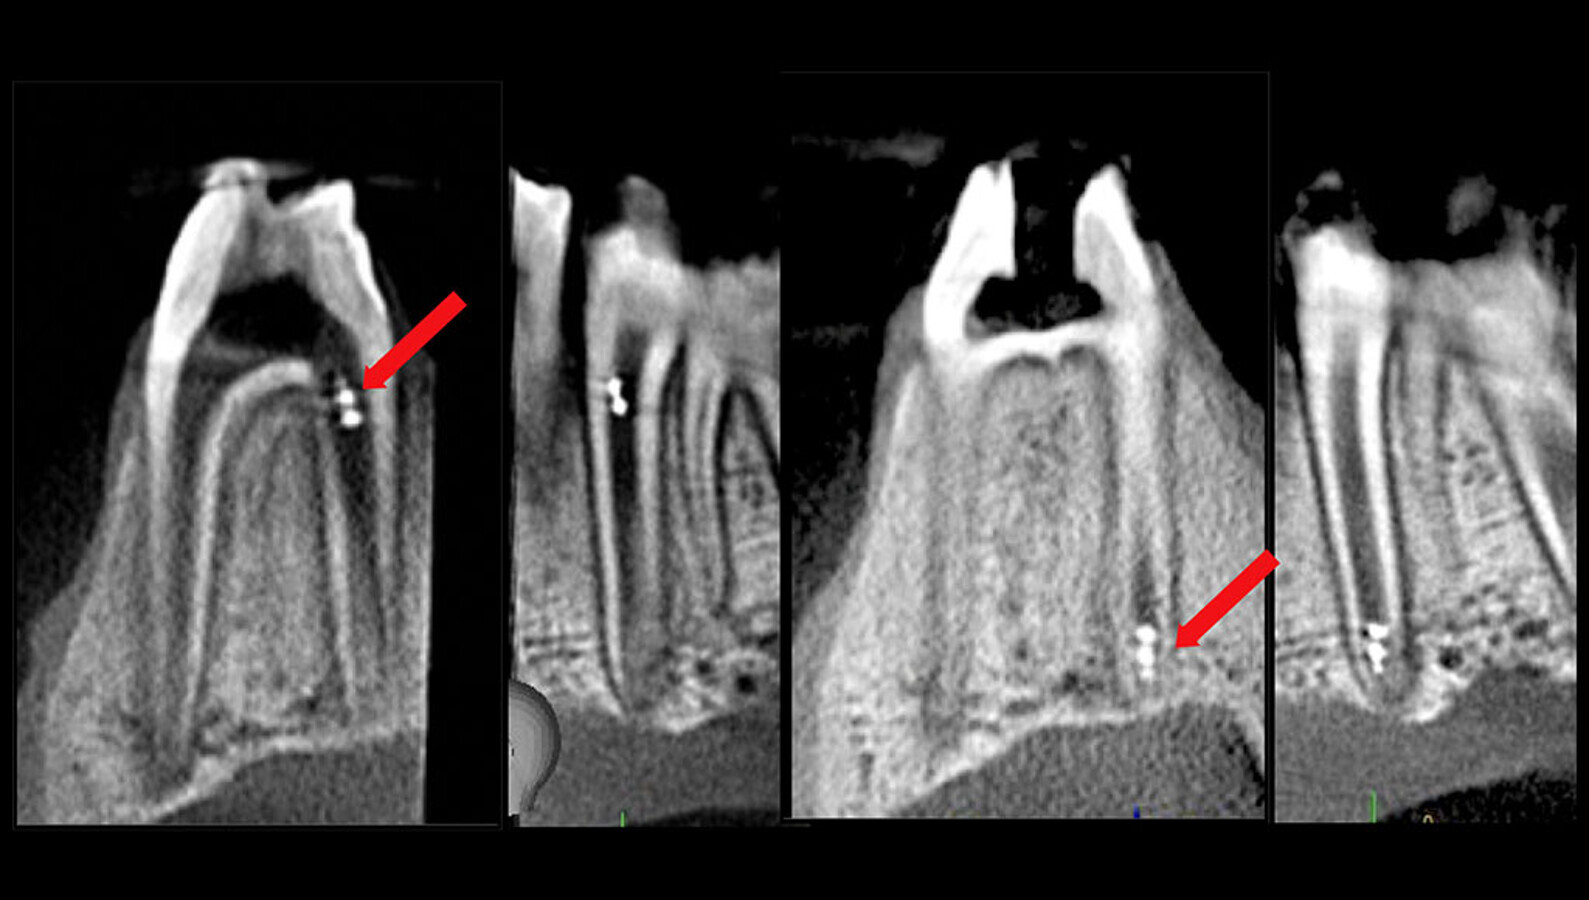

“Our findings demonstrate the feasibility of using the versatility of microrobotics to access difficult-to-reach endodontic surfaces to perform biofilm killing, removal and retrieval for microbial detection in real time. Furthermore, we demonstrate the feasibility of robot tracking inside the canal using current clinical imaging modalities,” he continued.

Magnetically actuated 3D-printed robots are controlled precisely to target the apical region of the root canal uninterrupted by the surrounding periodontium as visualised and tracked by CBCT. (Image: University of Pennsylvania)